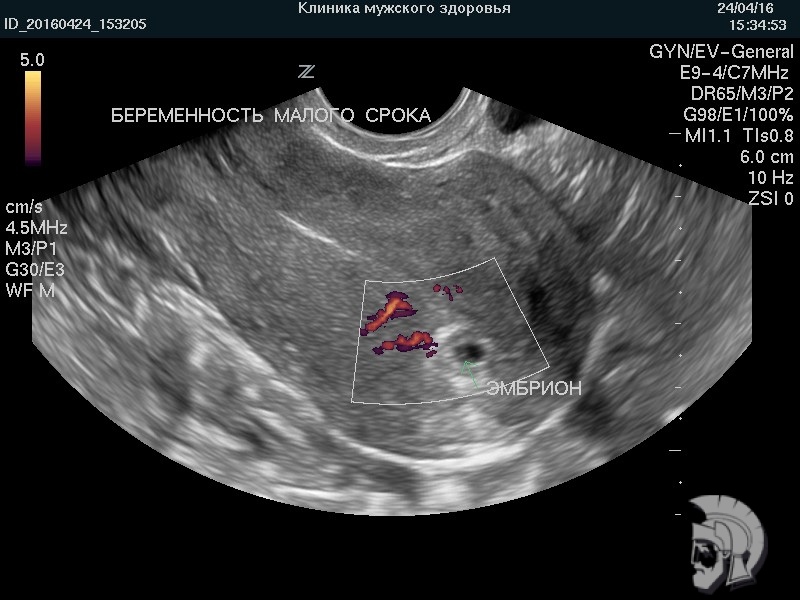

| Фото беременности малого срока. Эмбрион в виде пшеничного зерна указан стрелкой. При исследовании в режиме ДОППЛЕРа определяется маточный кровоток |

![]() |

Использование ультразвуковых аппаратов экспертного класса с режимами энергетического допплера и цветового ДОППЛЕРа позволяет врачам Курортной клиники мужского здоровья выявить пороки развития плода, маловодие и многоводие, нарушение МППК угрозу прерывания беременности на самых ранних этапах формирования.

Ответ: УЗИ беременности на ранних сроках позволяет определить форму плодного яйца и строение эмбриона, сердцебиение и особенности кровоснабжения эмбриона и плодного яйца, состояние шейки матки и тонус матки. На основании анализа вышеупомянутых данных врач УЗИ делает вывод о правильности развития эмбриона и течения беременности на ранних сроках.